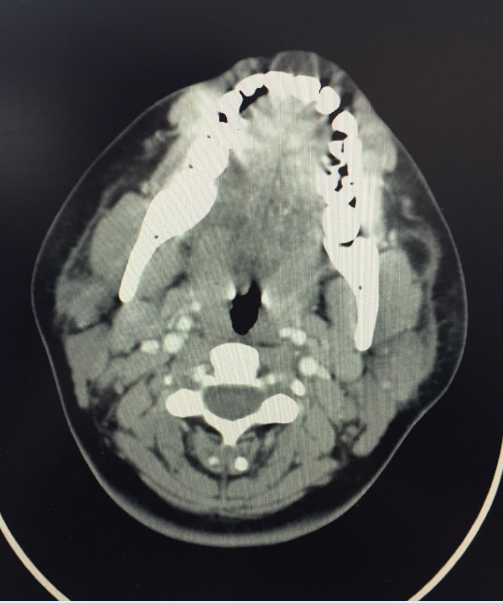

A neck computed tomography (CT) scan with contrast showed nonspecific, non-necrotic bilateral neck lymphadenopathy. The largest lymph nodes were along the right jugular chain, measuring 3 × 2 cm. A chest CT showed bilateral axillary lymphadenopathy, with the largest collection of lymph nodes in the left upper axillary region, measuring 3 × 2 cm. No mediastinal or hilar lymphadenopathy was noted.

Imaging may initially include an ultrasound, but CT evaluation of the lymph nodes is crucial. A chest X-ray is also important to evaluate for tuberculosis and malignancy. Yet, the most definitive diagnosis is obtained through cytologic evaluation from a fine-needle biopsy. Histologic findings should include paracortical necrosis, histocytes, lymphocytes, macrophages, and karyorrhexis.3 In addition, an excisional biopsy may be required.